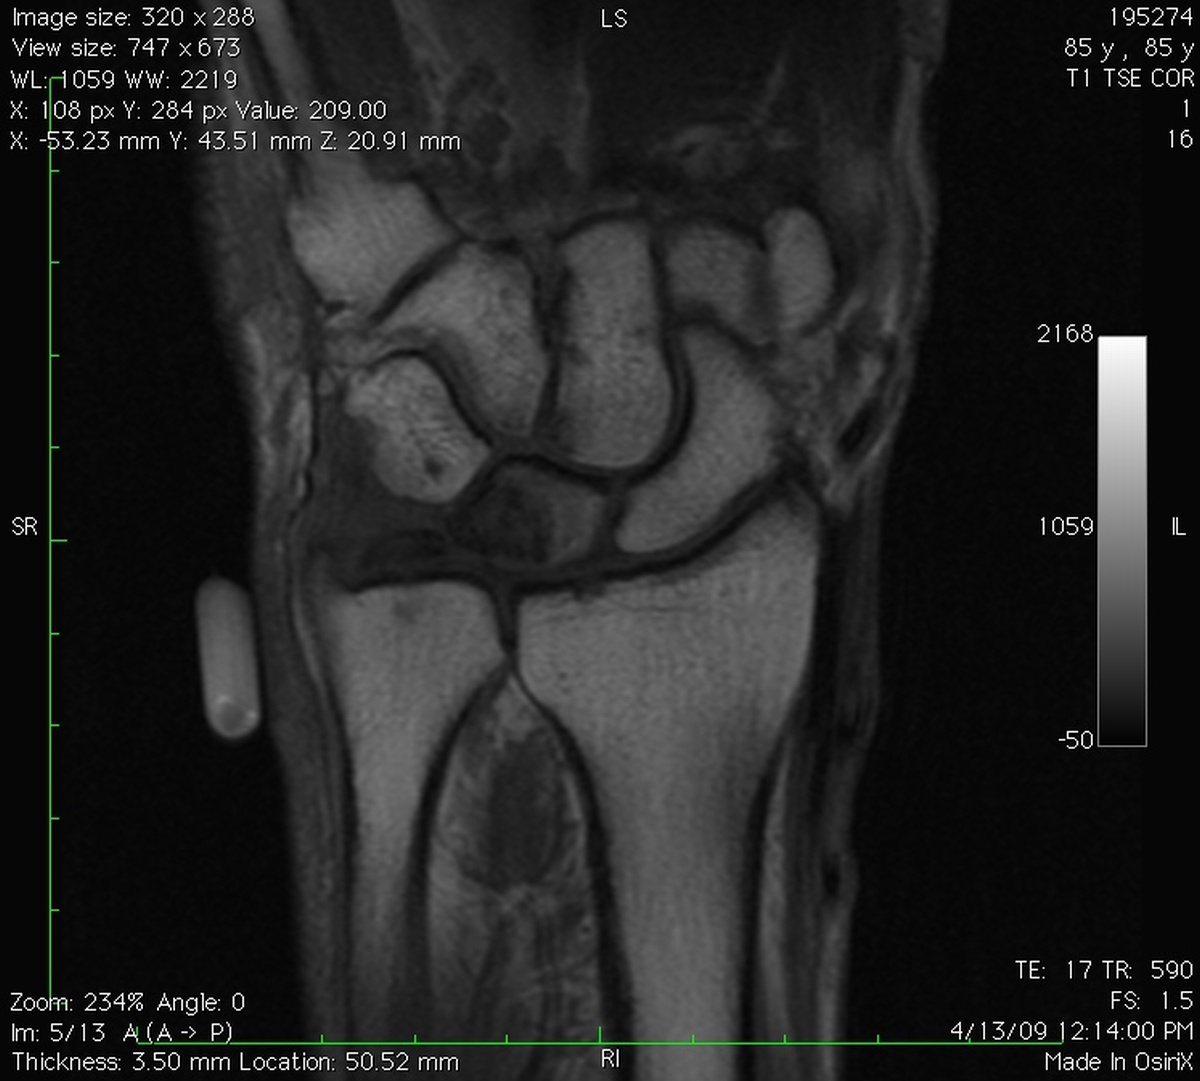

Clinical Example: Lunate Cyst

This imaging series was obtained for evaluation of a one month history of painful pronosupination in an active 85 year old man whose daily exercises include pushups.